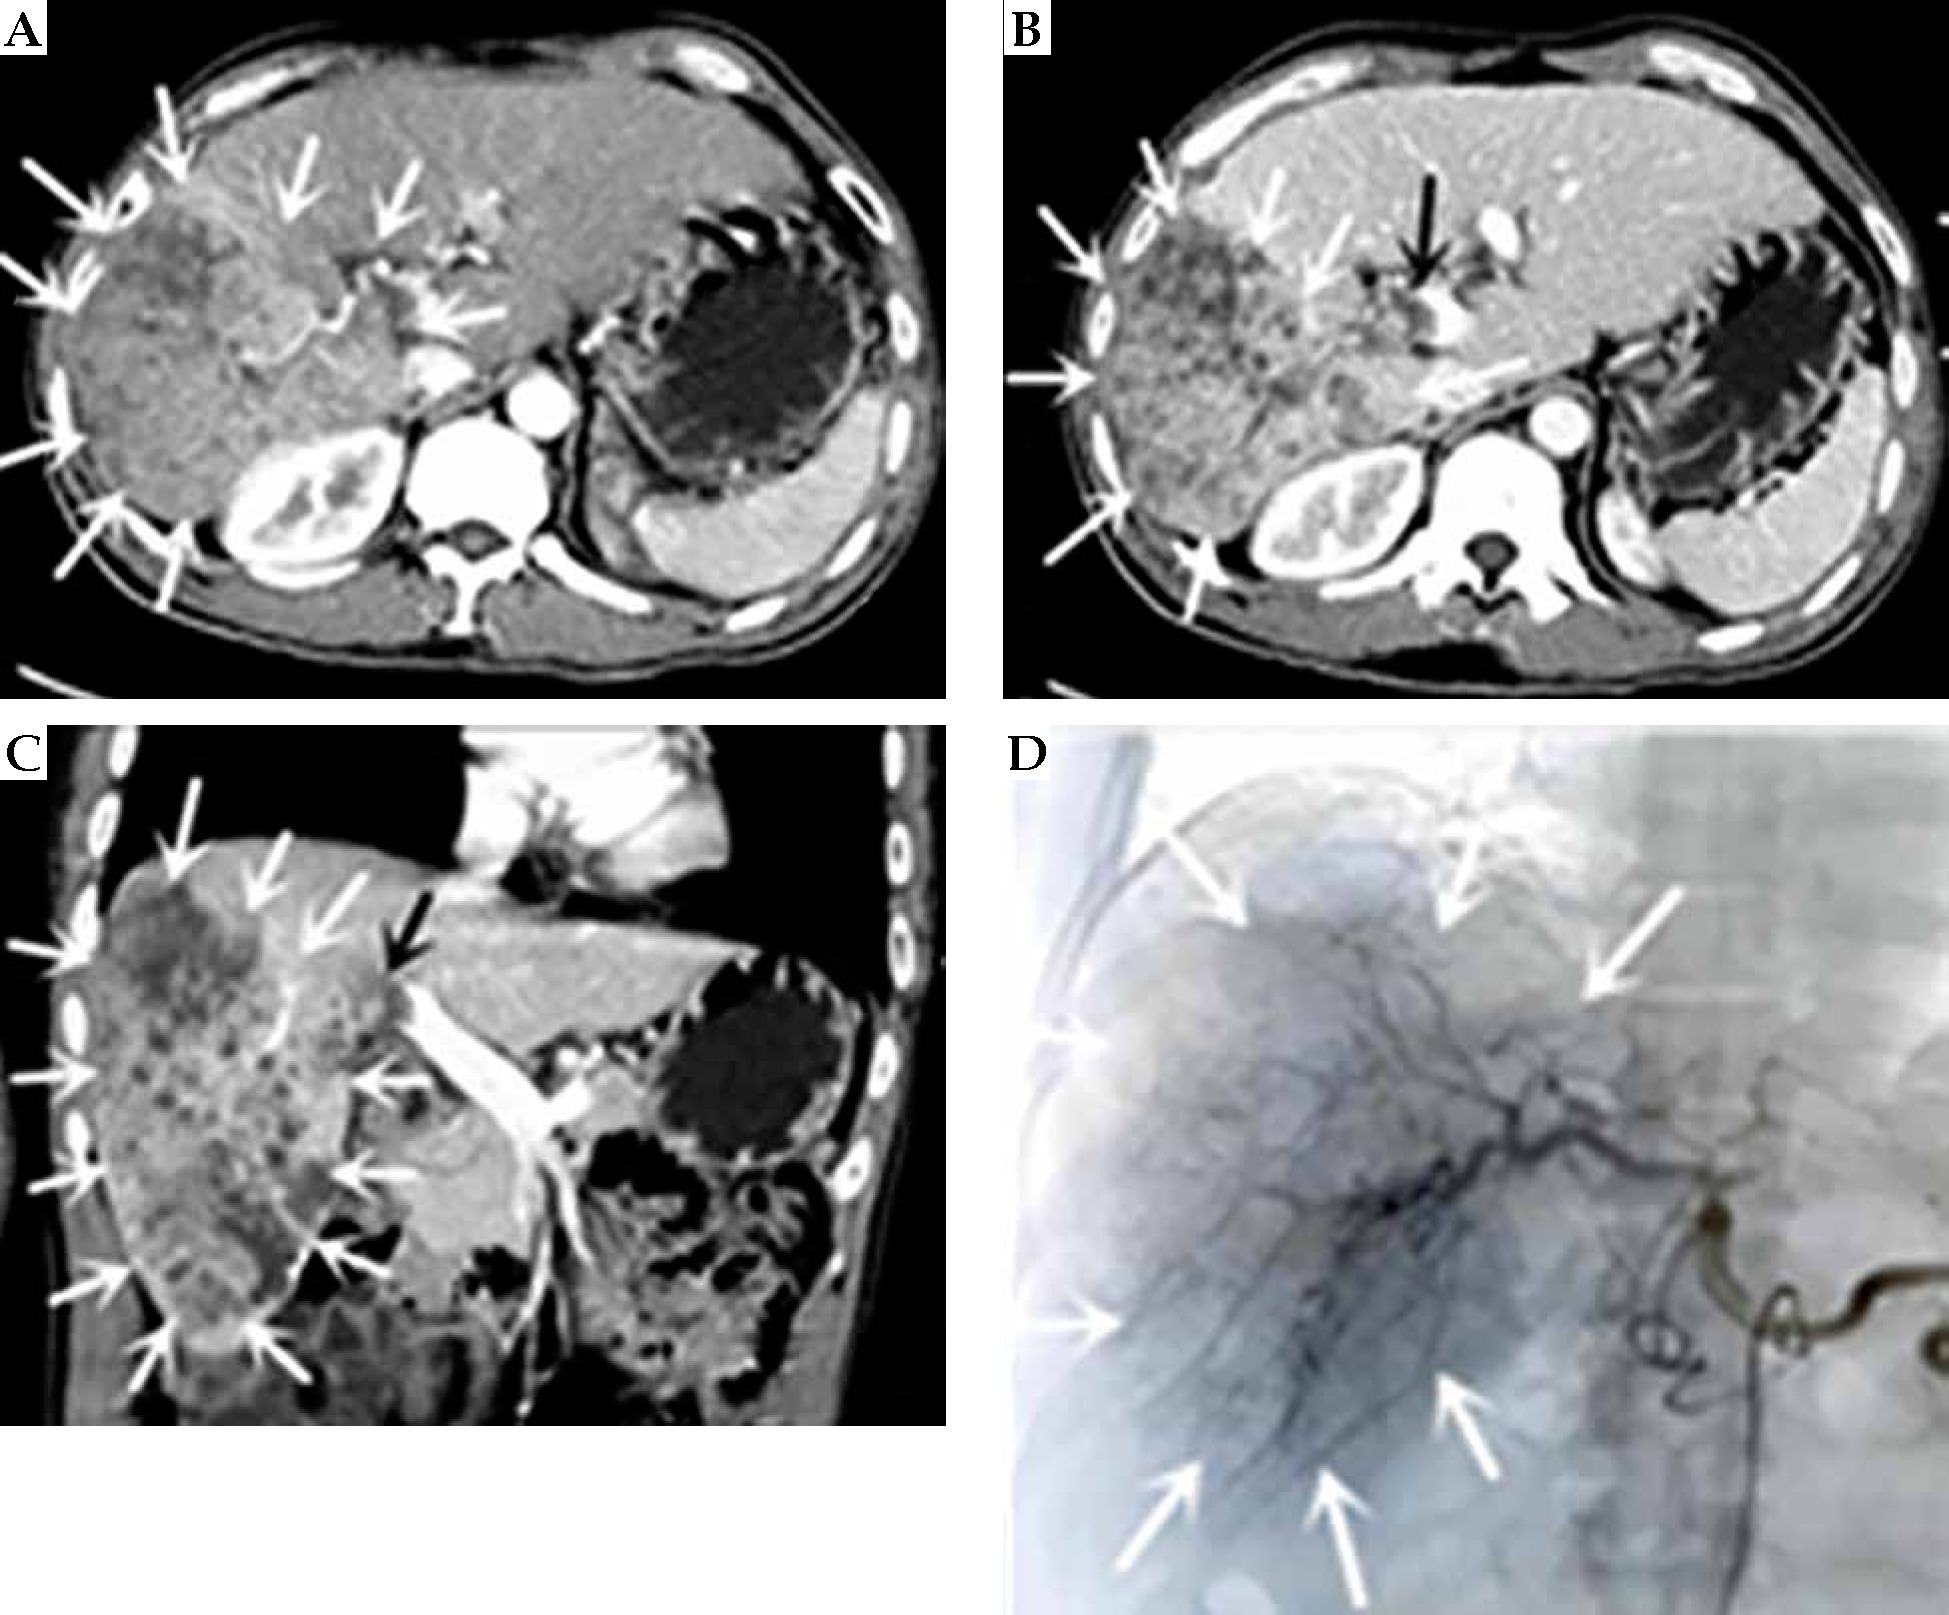

Fig. 3

Computed tomography (CT)-enhanced coronal images of portal phase before and after treatment. A) Before treatment. B) After more than 1 month of treatment. C) After more than 8 months of treatment. D) After more than 15 months of treatment. E) After more than 23 months of treatment. The white arrow indicate the liver cancer lesion, which is gradually shrinking, the black arrow is the portal cancer thrombus, which is gradually shrinking and disappearing, and the portal vein is partially open, the red arrow is the radioactive 125I particle

On April 8, 2021 (after more than 15 months of treatment), the patient’s pain disappeared, NRS score was 3, his weight increased by 10 kg, and PS score was 0. CT results showed complete necrosis and no enhancement of the intra-hepatic lesion, atrophy of the portal vein, partial opening of the main trunk, and the right branch of the portal vein to restore blood flow (Figure 3). AFP level decreased to normal range (1.96 ng/ml). The patient returned to the hospital for follow-ups on July 28, 2021, December 26, 2021, July 25, 2022, and March 23, 2023, with no complaints of discomfort (PS score, 0). AFP values maintained within normal range, and CT results indicated no recurrence or metastasis. At the last follow-up on March 23, 2023, the patient had a pain NRS of 0, weight 68 kg, PS score 0, AFP 1.96 ng/ml, liver function Child-Pugh score 5 (human blood albumin 38 g/l, total bilirubin 6.2 μmol/l, PT 11.6 s, no ascites or hepatic encephalopathy). After extensive evaluation, the patient’s disease was completely controlled, with no long-term recurrence or metastases and radical outcome. To date, PFS is 37 months.